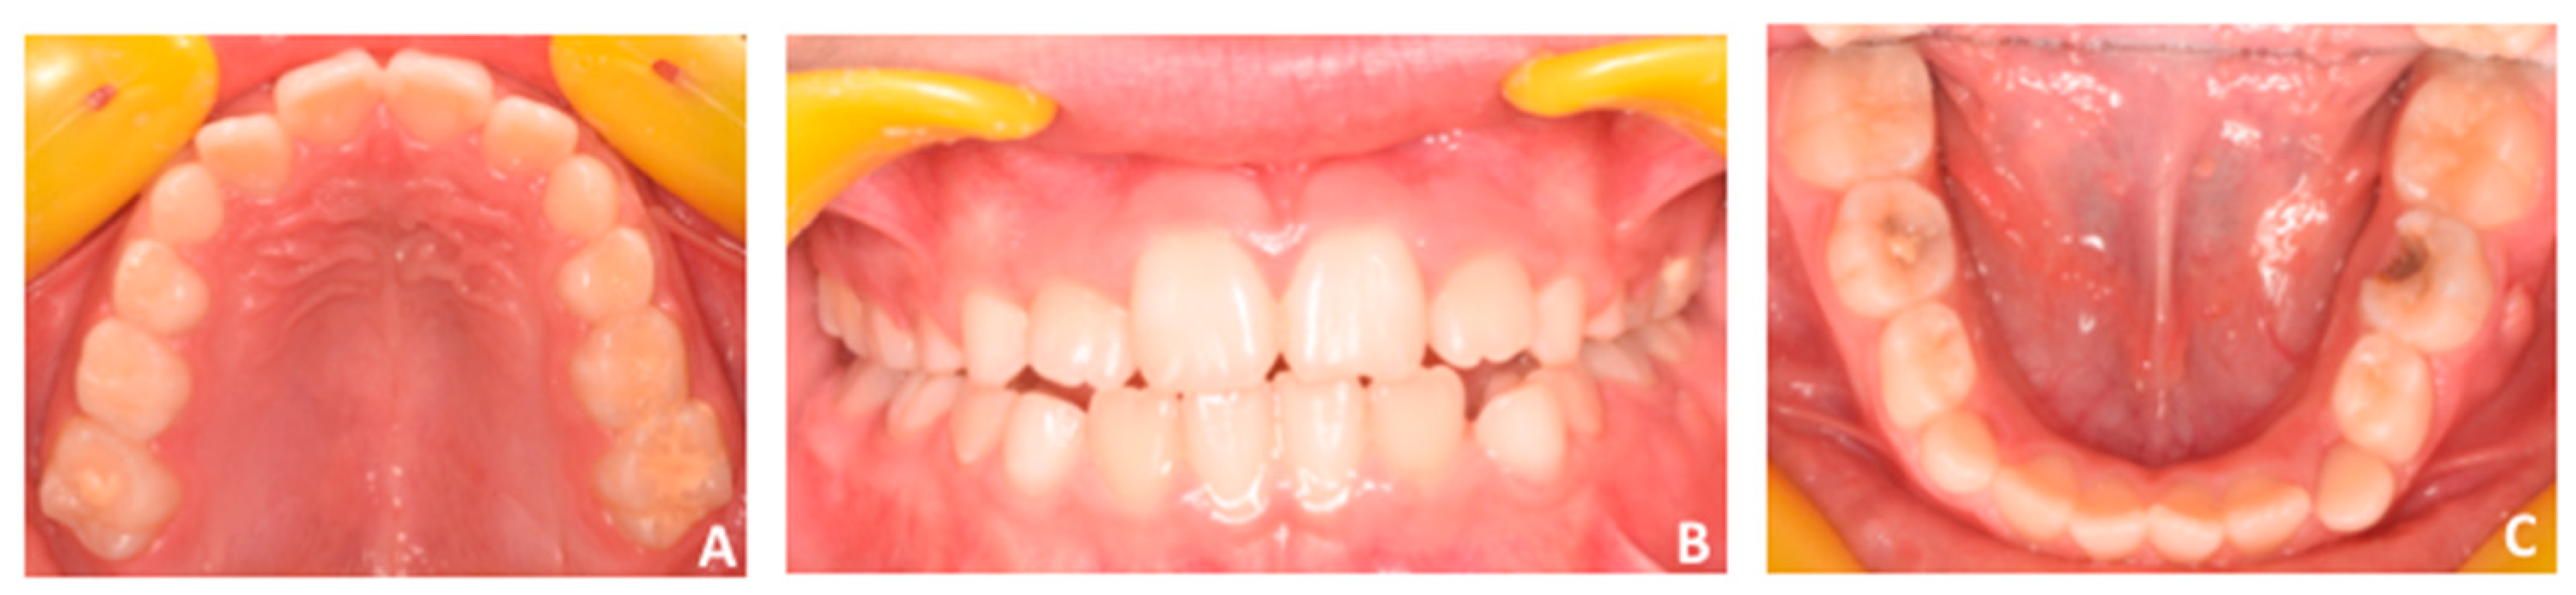

Facial examination revealed a eugnatic jaw growing pattern, slight retrusive profile with opened naso-labial angle, and labial competence (Figure 1). Intra-oral clinical examination, recorded with intra-oral photographs (Figure 2), showed early mixed dentition, a 5 mm anterior openbite, and posterior crossbite at the left side with small loss of coincidence between maxillary and mandibular midlines due to a slight shift of the mandible toward the crossbite side. Both the upper and lower midlines are coincident with the center of maxillary and mandibular arches. Functional examination revealed the presence of infant swallowing pattern with the tongue keeping an anterior position in an attempt to close the anterior space during swallowing or feeding.

Figure 2.

(A–C) Intra-oral examination. See the presence of anterior openbite (A). Additionally, posterior crossbite is present at the left side (B) with loss of coincidence between maxillary and mandibular midlines due to a slight shift of the mandible toward the crossbite side (left side). Both the upper and lower midlines are coincident with the center of maxillary (A) and mandibular (B) arches.

(A–C) Intra-oral examination. In particular, see the absence of crossbite at the right side (A) and the coincidence between maxillary and mandibular midlines (B).